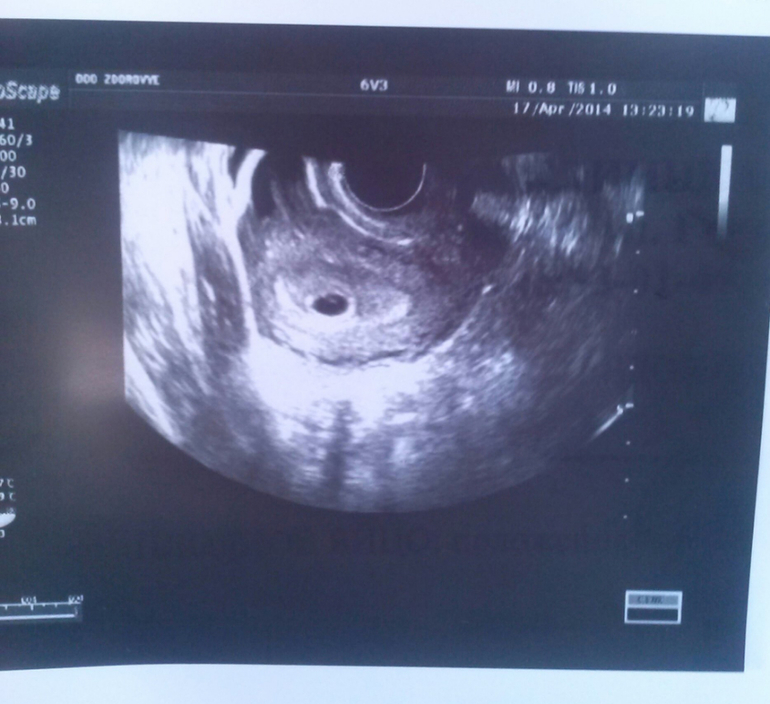

Мое УЗИ

Девчат, гляньте! Не могу понять, что написано рядом с контурами?

И вообще,все ли нормально?

Контуры -ровный или ровные. Просто у врача такой почерк,она и в слове ПРАВИЛЬНАЯ,что выше так же букву Р пишет.Обратите внимание. А вообще я свое узи первое достала и посмотрела у меня даже цифры с вашими почти совпадают.Так вот у меня тоже написано,что контуры -ровные. Все у вас хорошо.

спасибо) а КТР не маловато? Начиталась, что маленький. Срок акушерский в день узи был 5недель и 2 дня

У меня тоже при первом УЗИ так же КТР,а срок написано 5-6 недель. Сейчас уже 35 неделя идет, говорят,что все хорошо. Значит и тогда было все хорошо,а следовательно и у вас так же будет.